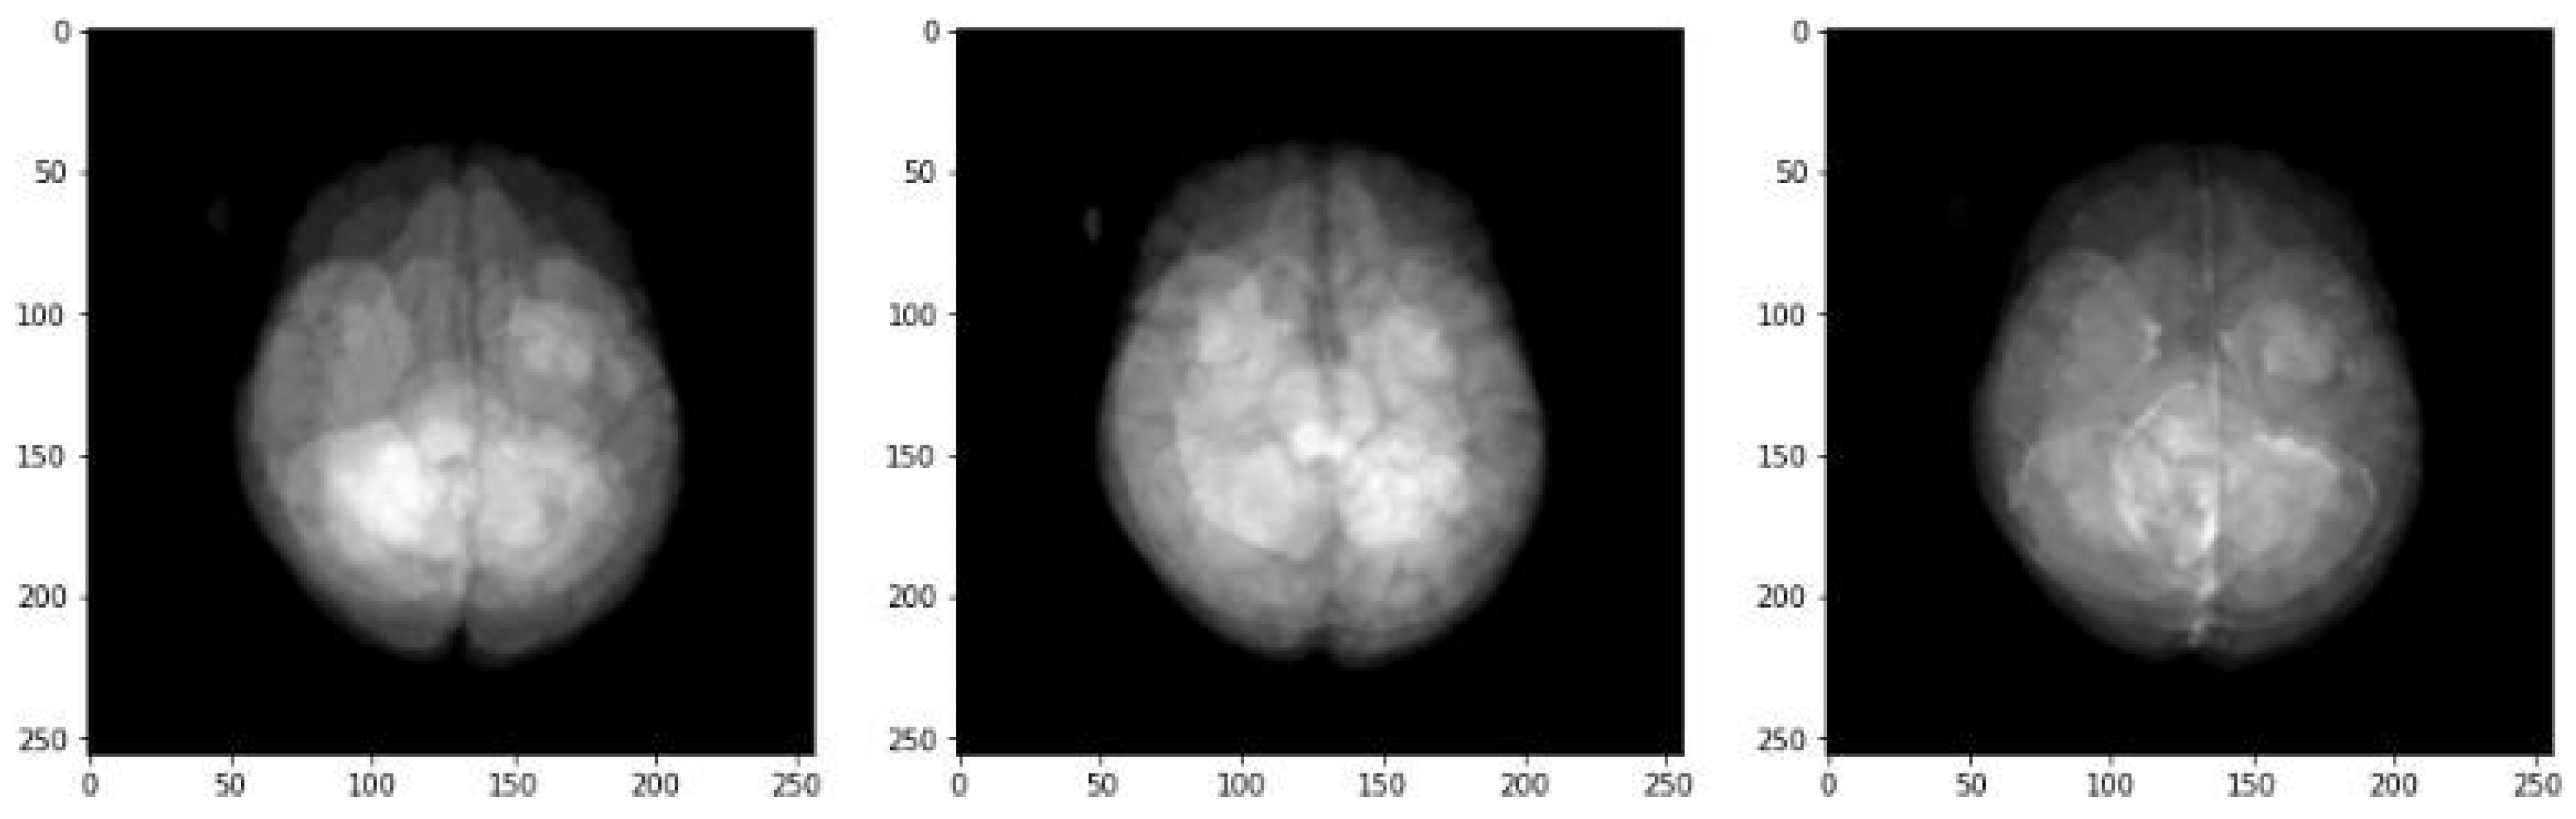

Sample Model Predictions